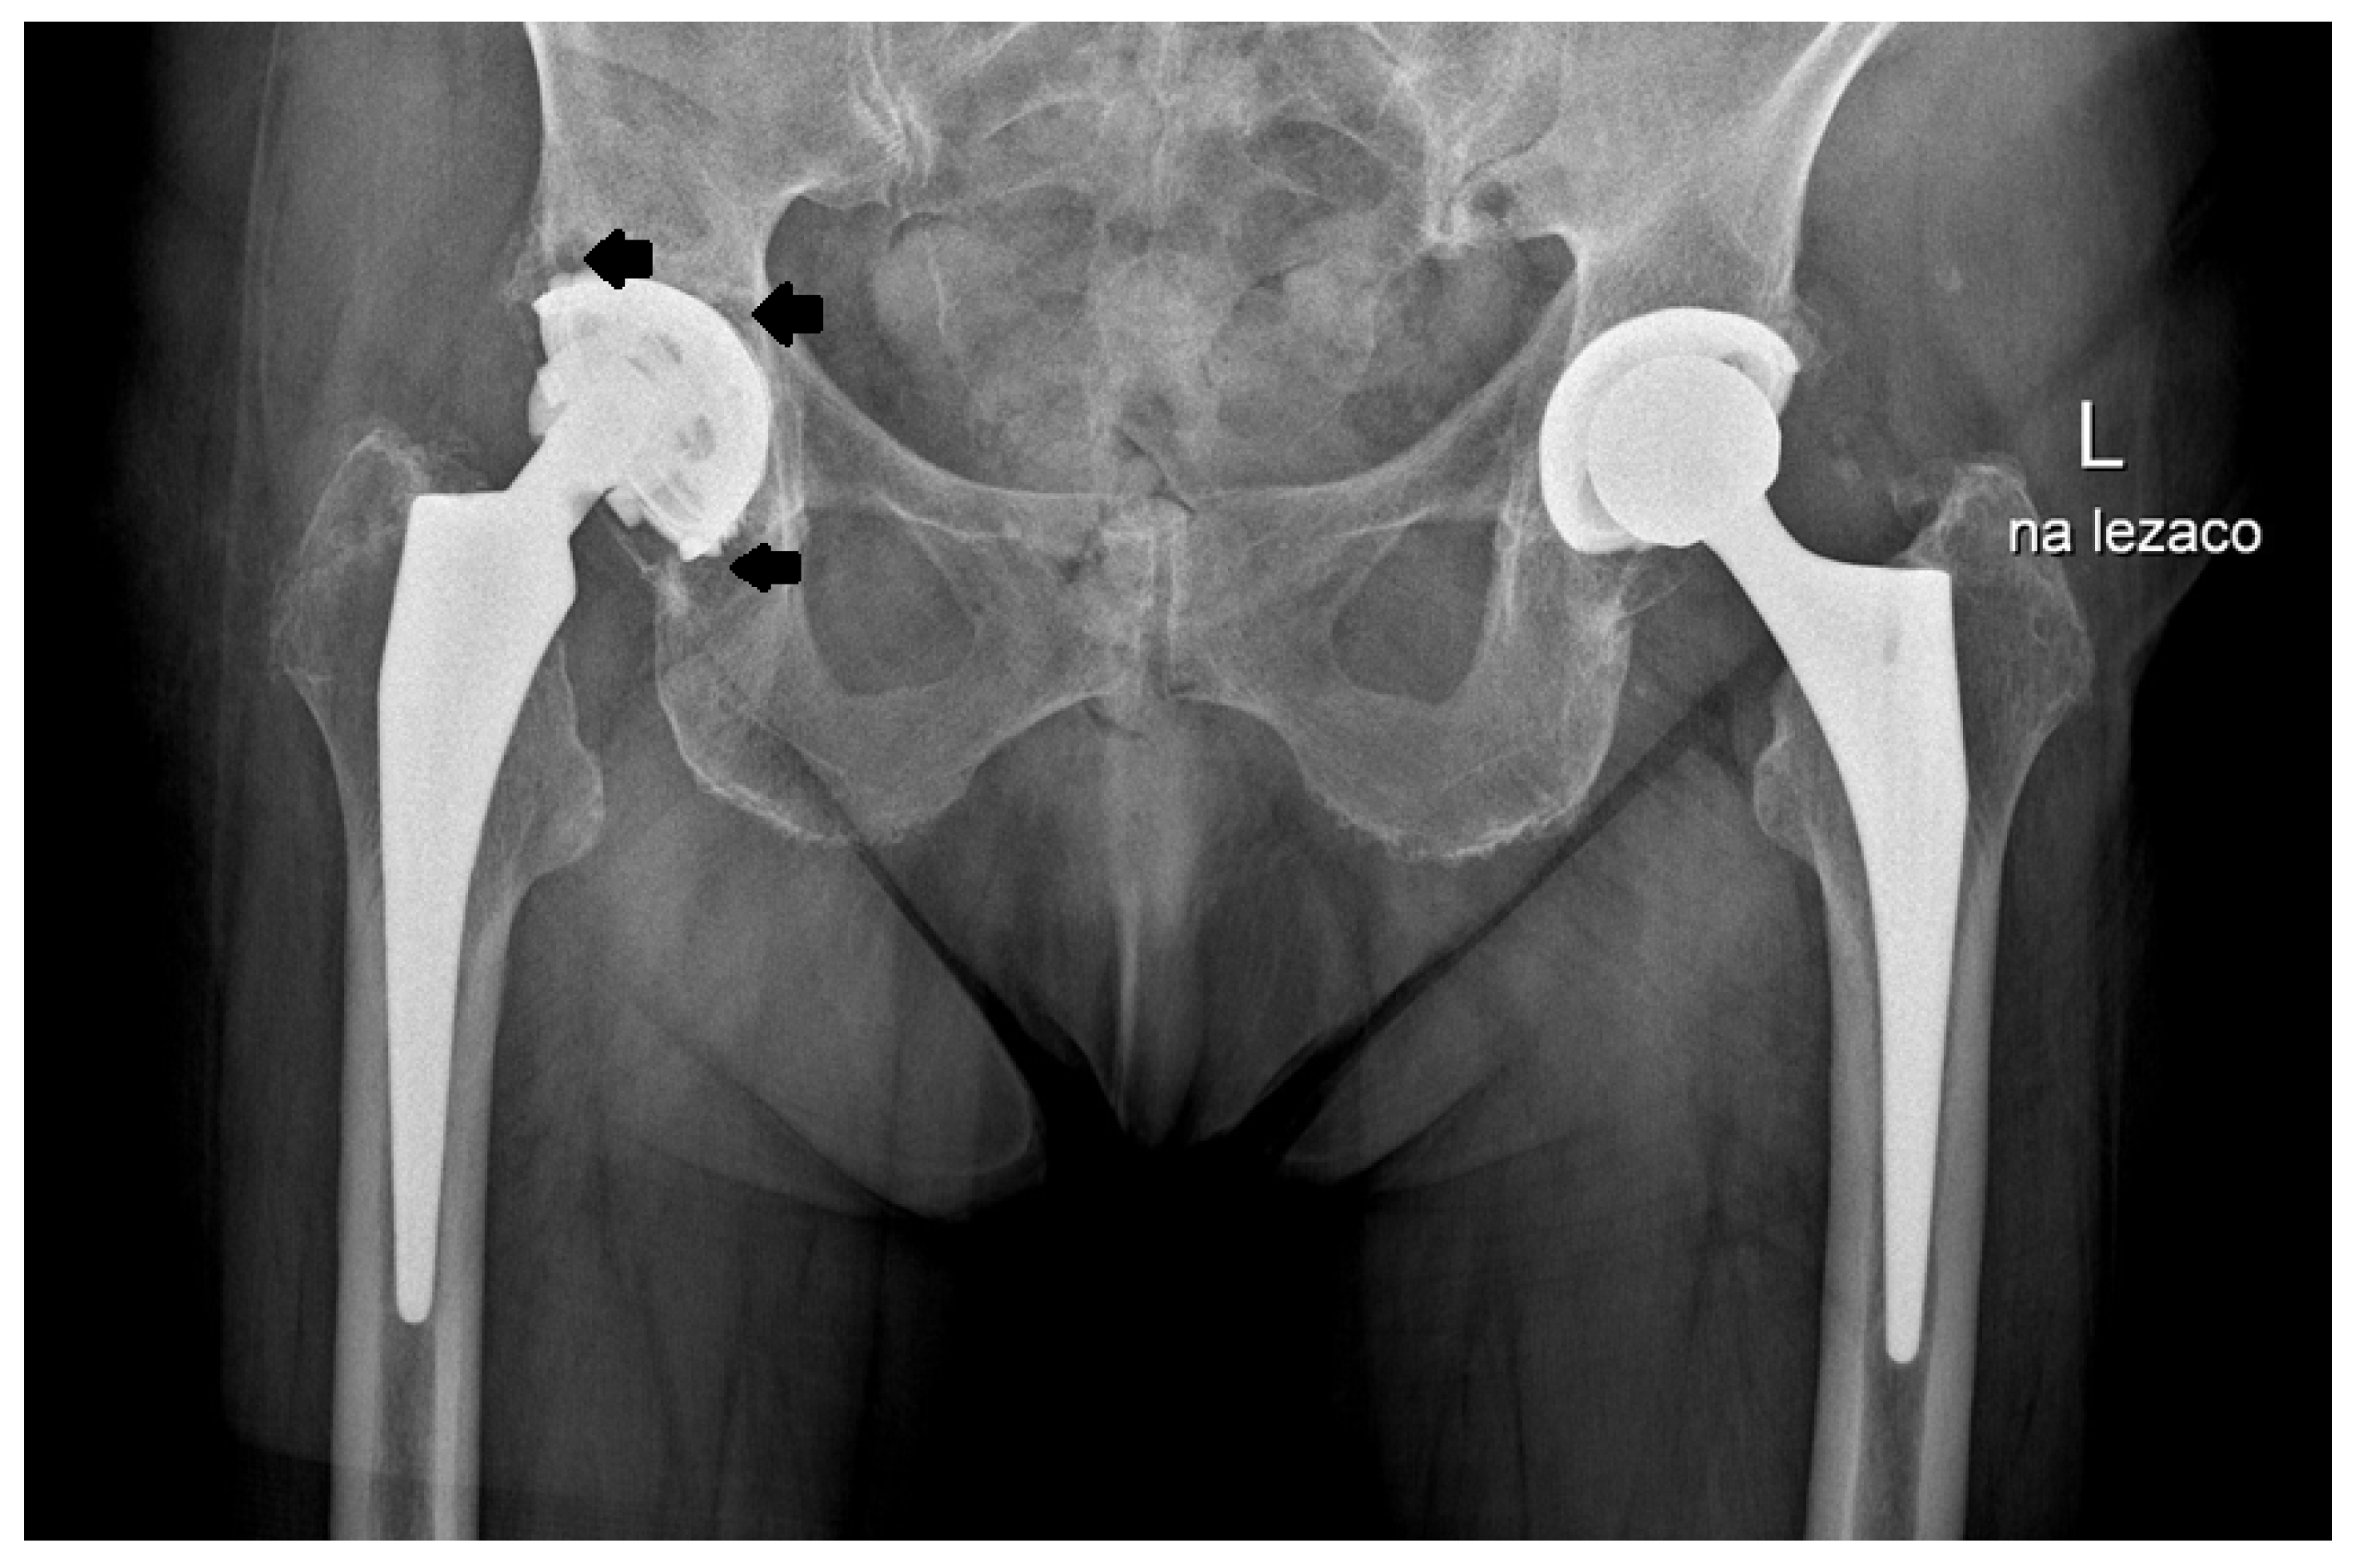

2.2. Design of the L-Cup Acetabular Component

3. Results

4. Discussion